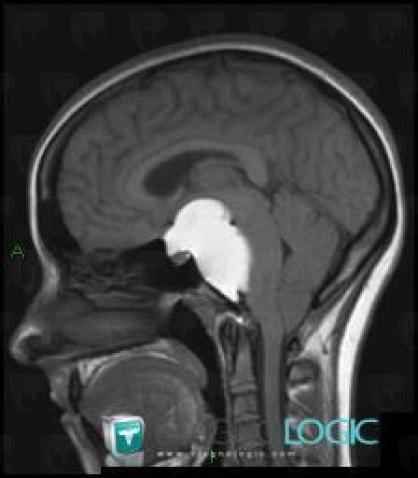

Craniopharyngiome, Angle ponto cérébelleux, IRM

Voici les informations spécifiques à l'image clé ci dessus:

- Diagnostic Craniopharyngiome, Localisation(s) Angle ponto cérébelleux, comportant les gammes Masse de l'angle ponto cérébelleux